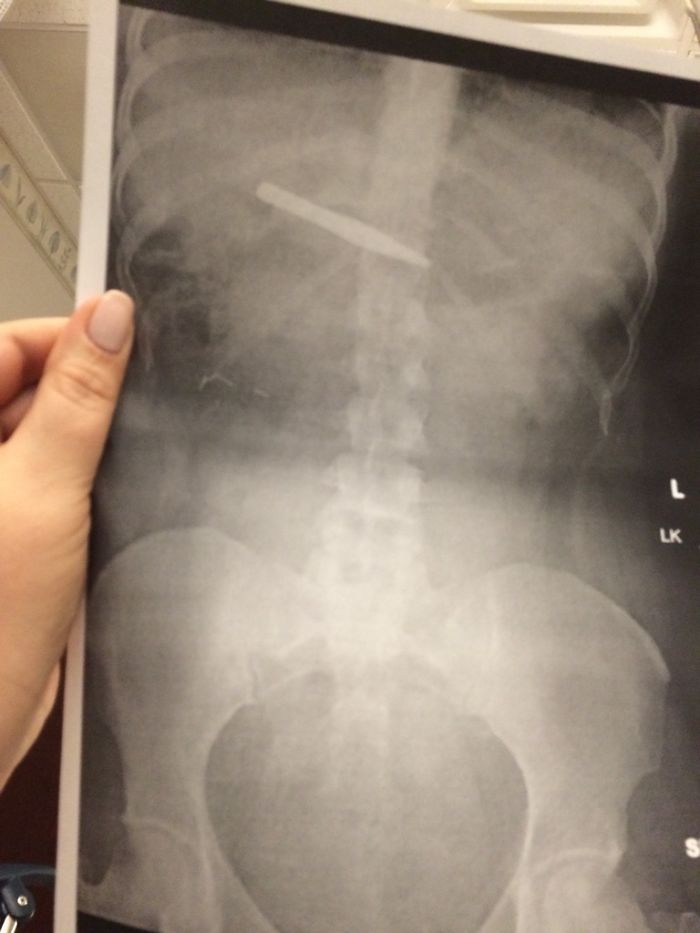

Me he tragado unas pinzas

Mi novio vino al hospital a verme antes de la operación y le pregunté si había dicho en recepción que venía a ver a la chica que se tragó unas pinzas. Respondió: "¡Por supuesto! ¿Cuándo voy a poder volver a usar esa frase si no?"